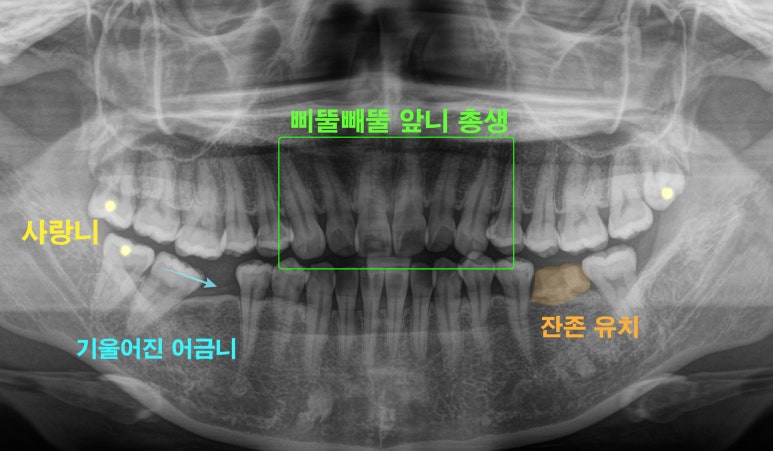

엑스레이를 보면서

한 번 더 정리해 보자면

이 환자가 해결해야 될 문제는

크게 4가지 정도가 있습니다.

삐뚤빼뚤한 앞니 총생

왼쪽 아래 잔존 유치

오른쪽 아래 어금니 기울어짐으로 공간 부족

충치가 생긴 사랑니